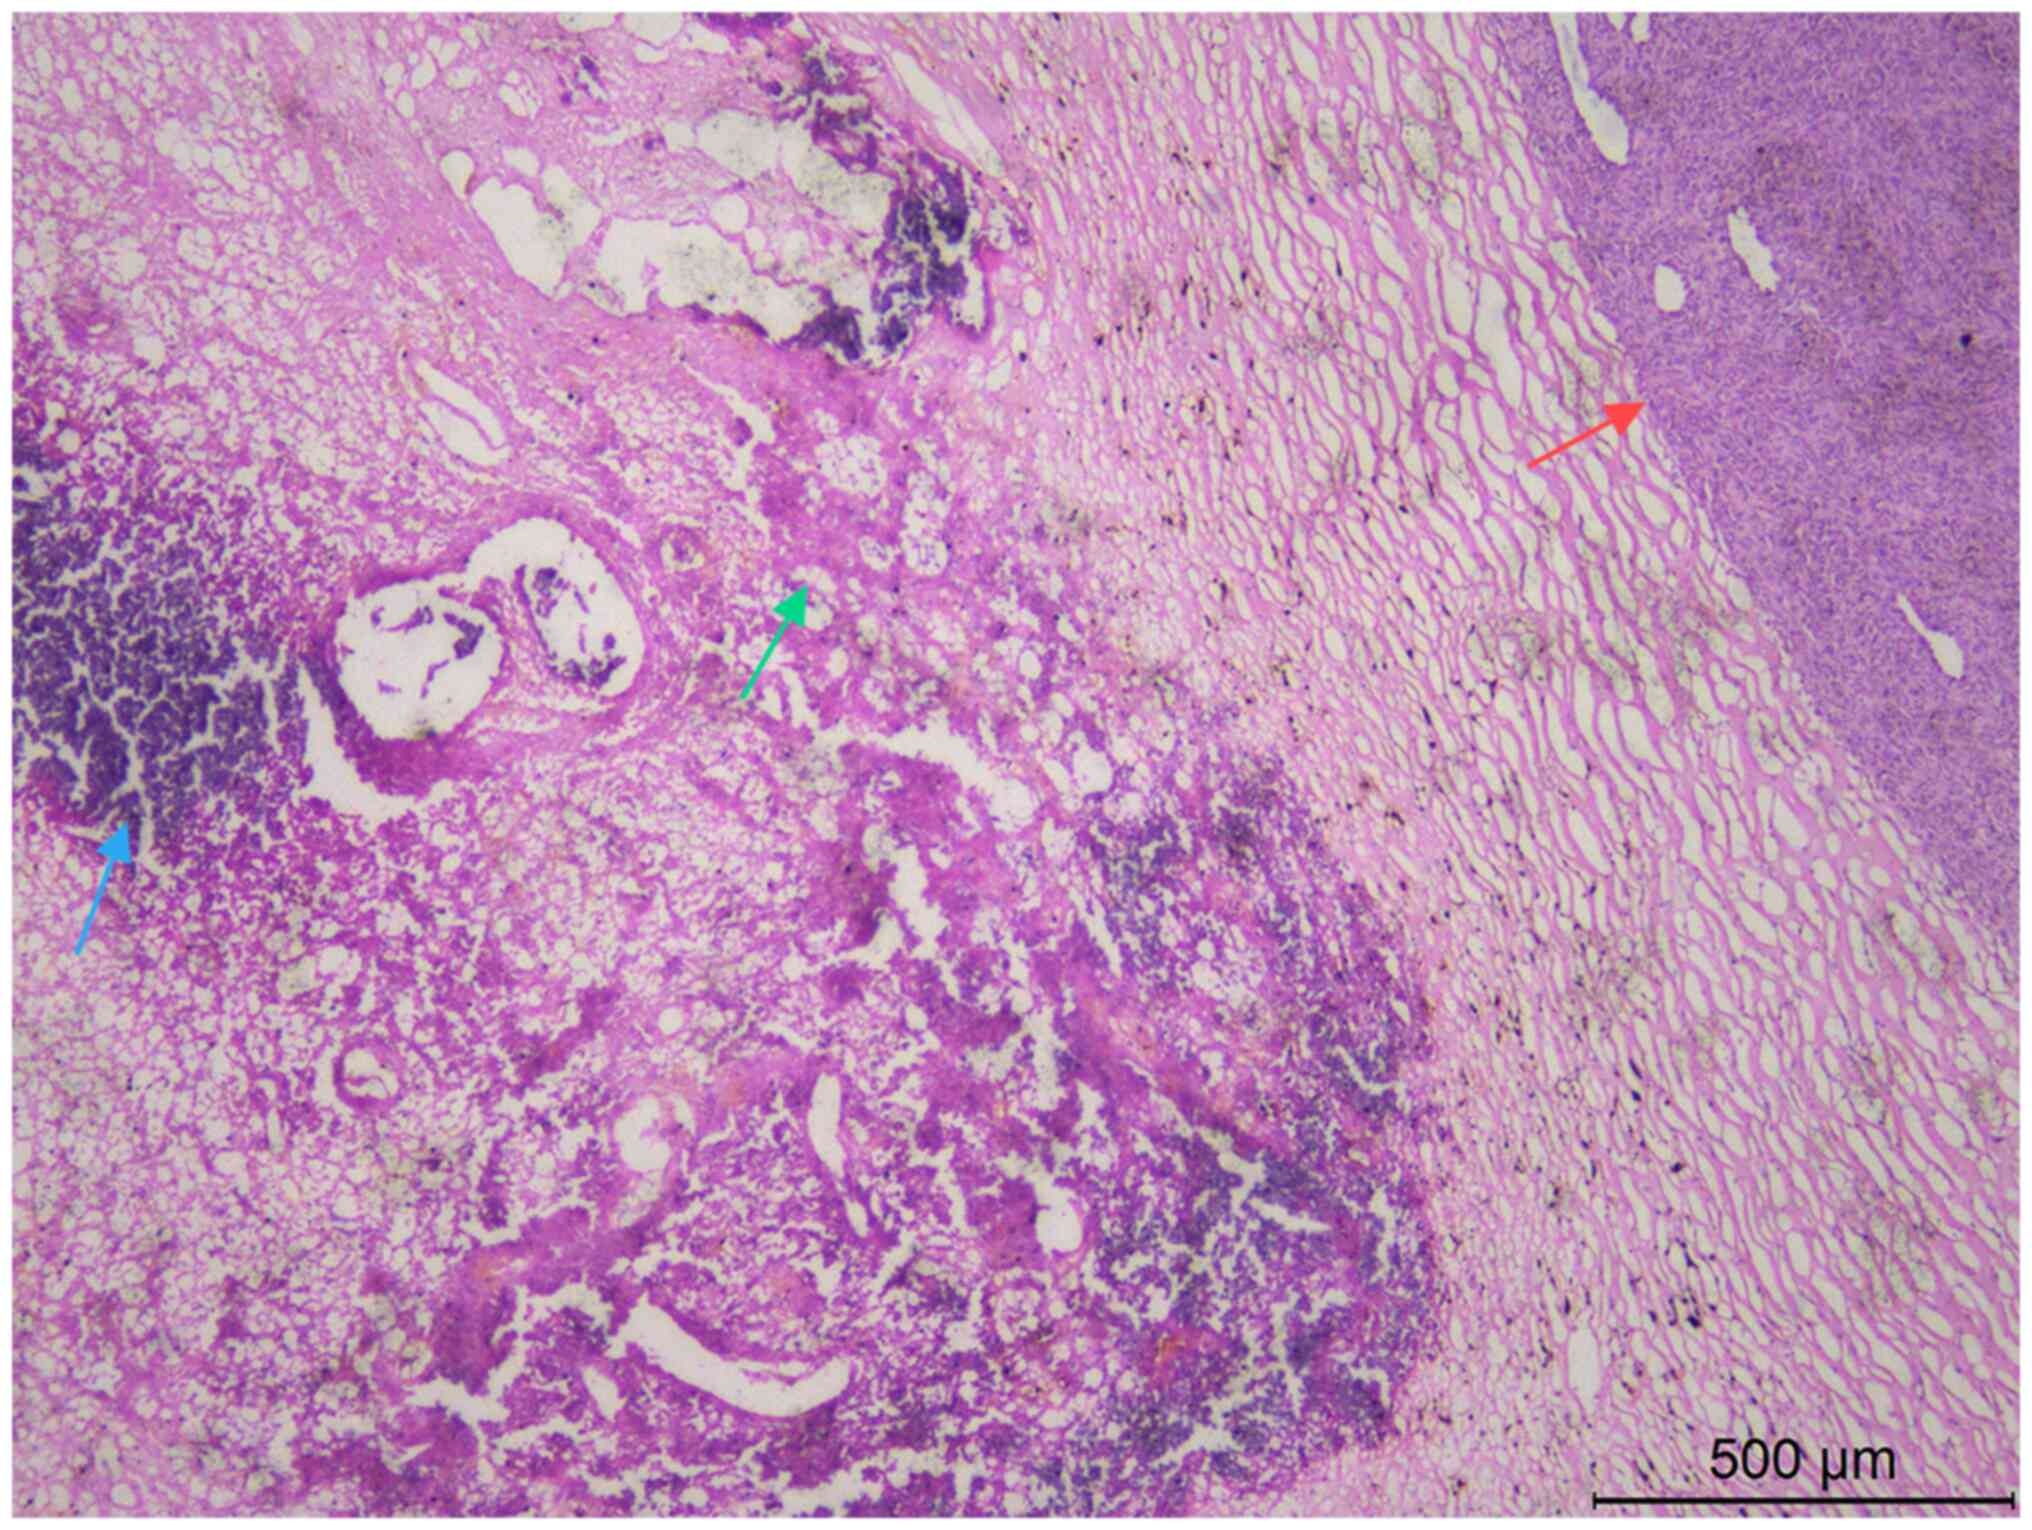

Figure 3.

Hematoxylin and eosin staining showing lamellar necrosis and calcification in some areas of the tumor. Scale bar, 500 µm. The red arrow indicates tumor cells, the green arrow indicates necrosis and the blue arrow indicates calcification.

The pathological findings were of a mass of gray-white and gray-red fragmented tissue measuring 25.0×20.0×8.0 cm, with some well-defined areas. The cut surface had a fish meat-like appearance, gray-white and gray-red in color, with a solid and soft texture. The specimens were fixed in 4% neutral formalin at room temperature for 12 h, followed by routine dehydration, paraffin embedding and sectioning at a thickness of 5 µm. Hematoxylin and eosin staining was then performed at room temperature for 5 min each. Examination under a light microscopic examination revealed an incomplete tumor capsule with infiltrative growth, and tumor cells were observed to invade the surrounding muscle and adipose tissue. The tumor predominantly consisted of long spindle cells arranged in bundles, featuring darkly stained nuclei, inconspicuous nucleoli, mitosis and eosinophilic cytoplasm (Fig. 2). In a few regions, the tumor cells were naive, stellate or irregularly shaped, with interstitial mucinous edema-like changes. Some tumor cells showed lamellar necrosis and calcification (Fig. 3).